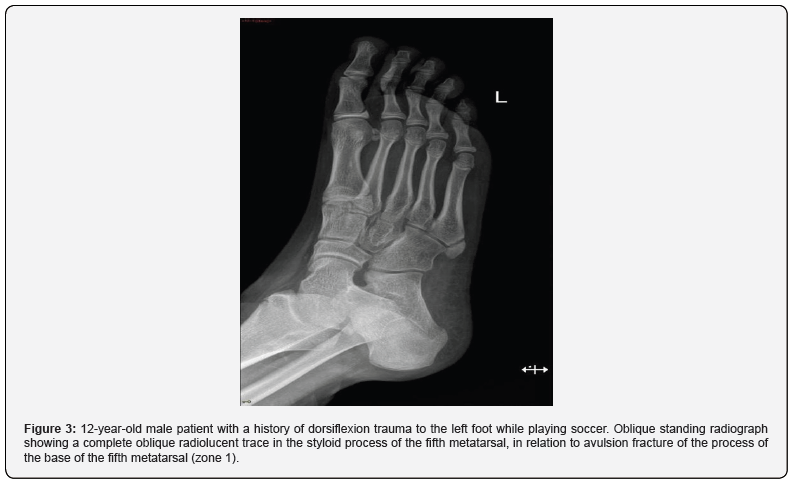

The fracture of the fifth metatarsal is the common pathology of this bone, it occupies 35% of the frequency of foot fractures and 70% of the metatarsal bones. There are several classifications, currently the Dameron-Lawrance-Botte classification is recommended since it allows characterization of the affected anatomical area, its management and prognosis. This classification divides fractures into three groups according to the area they affect; zone 1: fracture - avulsion of the styloid process of the 5th metatarsal (Figure 3). It may or may not have involvement of the metatarsocuboid joint; the mechanism that favors its presentation is a sudden traction of the peroneus brevis in forced inversion. Conservative management until intramedullary nailing [7,8].